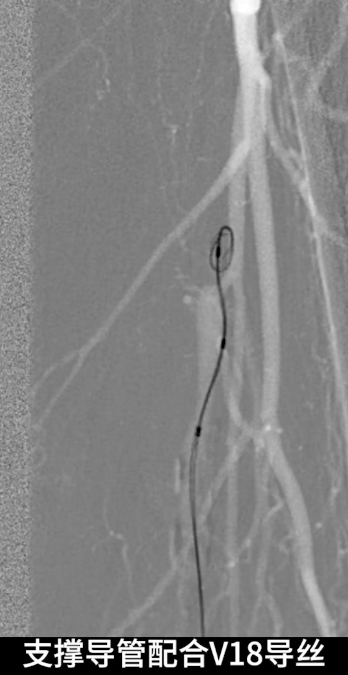

首先尝试顺行通过股浅动脉闭塞段,导丝进入内膜下,开通失败;遂改为逆穿策略,以支撑导管配合V18导丝逆行通过股浅动脉闭塞段,最终与近端股浅动脉真腔成功对接,建立安全操作轨道。